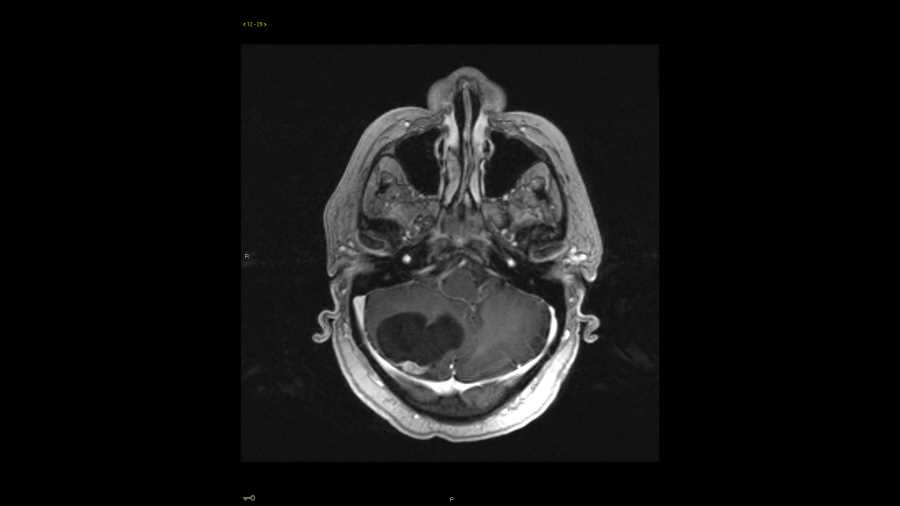

Meningioma

These images show a large T2 hyperintense, multi-septated, cystic, extra-axial mass along the right frontal convexity with significant mass effect on the subjacent brain, but no evidence of edema. This indicates a slow growing process and is compatible with a meningioma. Of importance from a surgical standpoint, there is no evidence of superior sagittal sinus infiltration. Meningiomas can be cystic which may represent areas of degeneration or necrosis. The differential in this case includes a hemangiopericytoma, but these are usually locally aggressive, features which are not seen in this case.